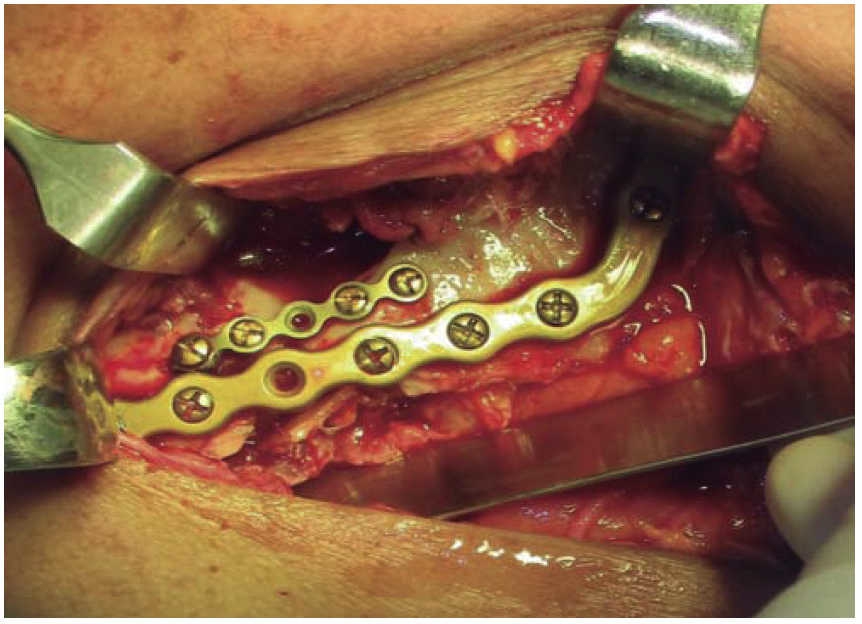

The second surgical event took place seven days later, performing extraoral approach. The fracture was reduced and bone edges were fixated with a 2.4 precontoured mandibular reconstruction plate (Figure 6). Occlusal stability was verified before suturing tissues and bar arches were removed (Figure 7). The patient remained in hospital for seven days, after which he showed suitable occlusion and appropriate healing. Suture points were then removed, a control study was performed and the patient was discharged. The patient did not attend control visits due to the fact that he was incarcerated.

Treatment was initiated with immunization, antibiotic therapy, analgesia, extraction of septic foci and mechanical cleansing of the wound. The patient lacked removable or partial prostheses, so in order to establish inter-maxillary relationship and facial height, gunning splints were manufactured in order to establish inter-maxillary relationship (Figure 13). After ten days of initial treatment, the patient exhibited suitable alveolar healing, with presence of non-fetid secretion at the level of the mandibular wound. The second procedure was then undertaken with extra-oral approach; a 2.4 mandibular reconstruction plate and a 2.0 bone segment plate were used (Figures 14 and 15). The patient was discharged, and she attended periodic assessment visits which showed suitable healing (Figure 16) and adequate mandibular mobility. Three weeks after reconstruction, the patient was instructed to initiate prosthetic treatment in order to achieve rehabilitation.